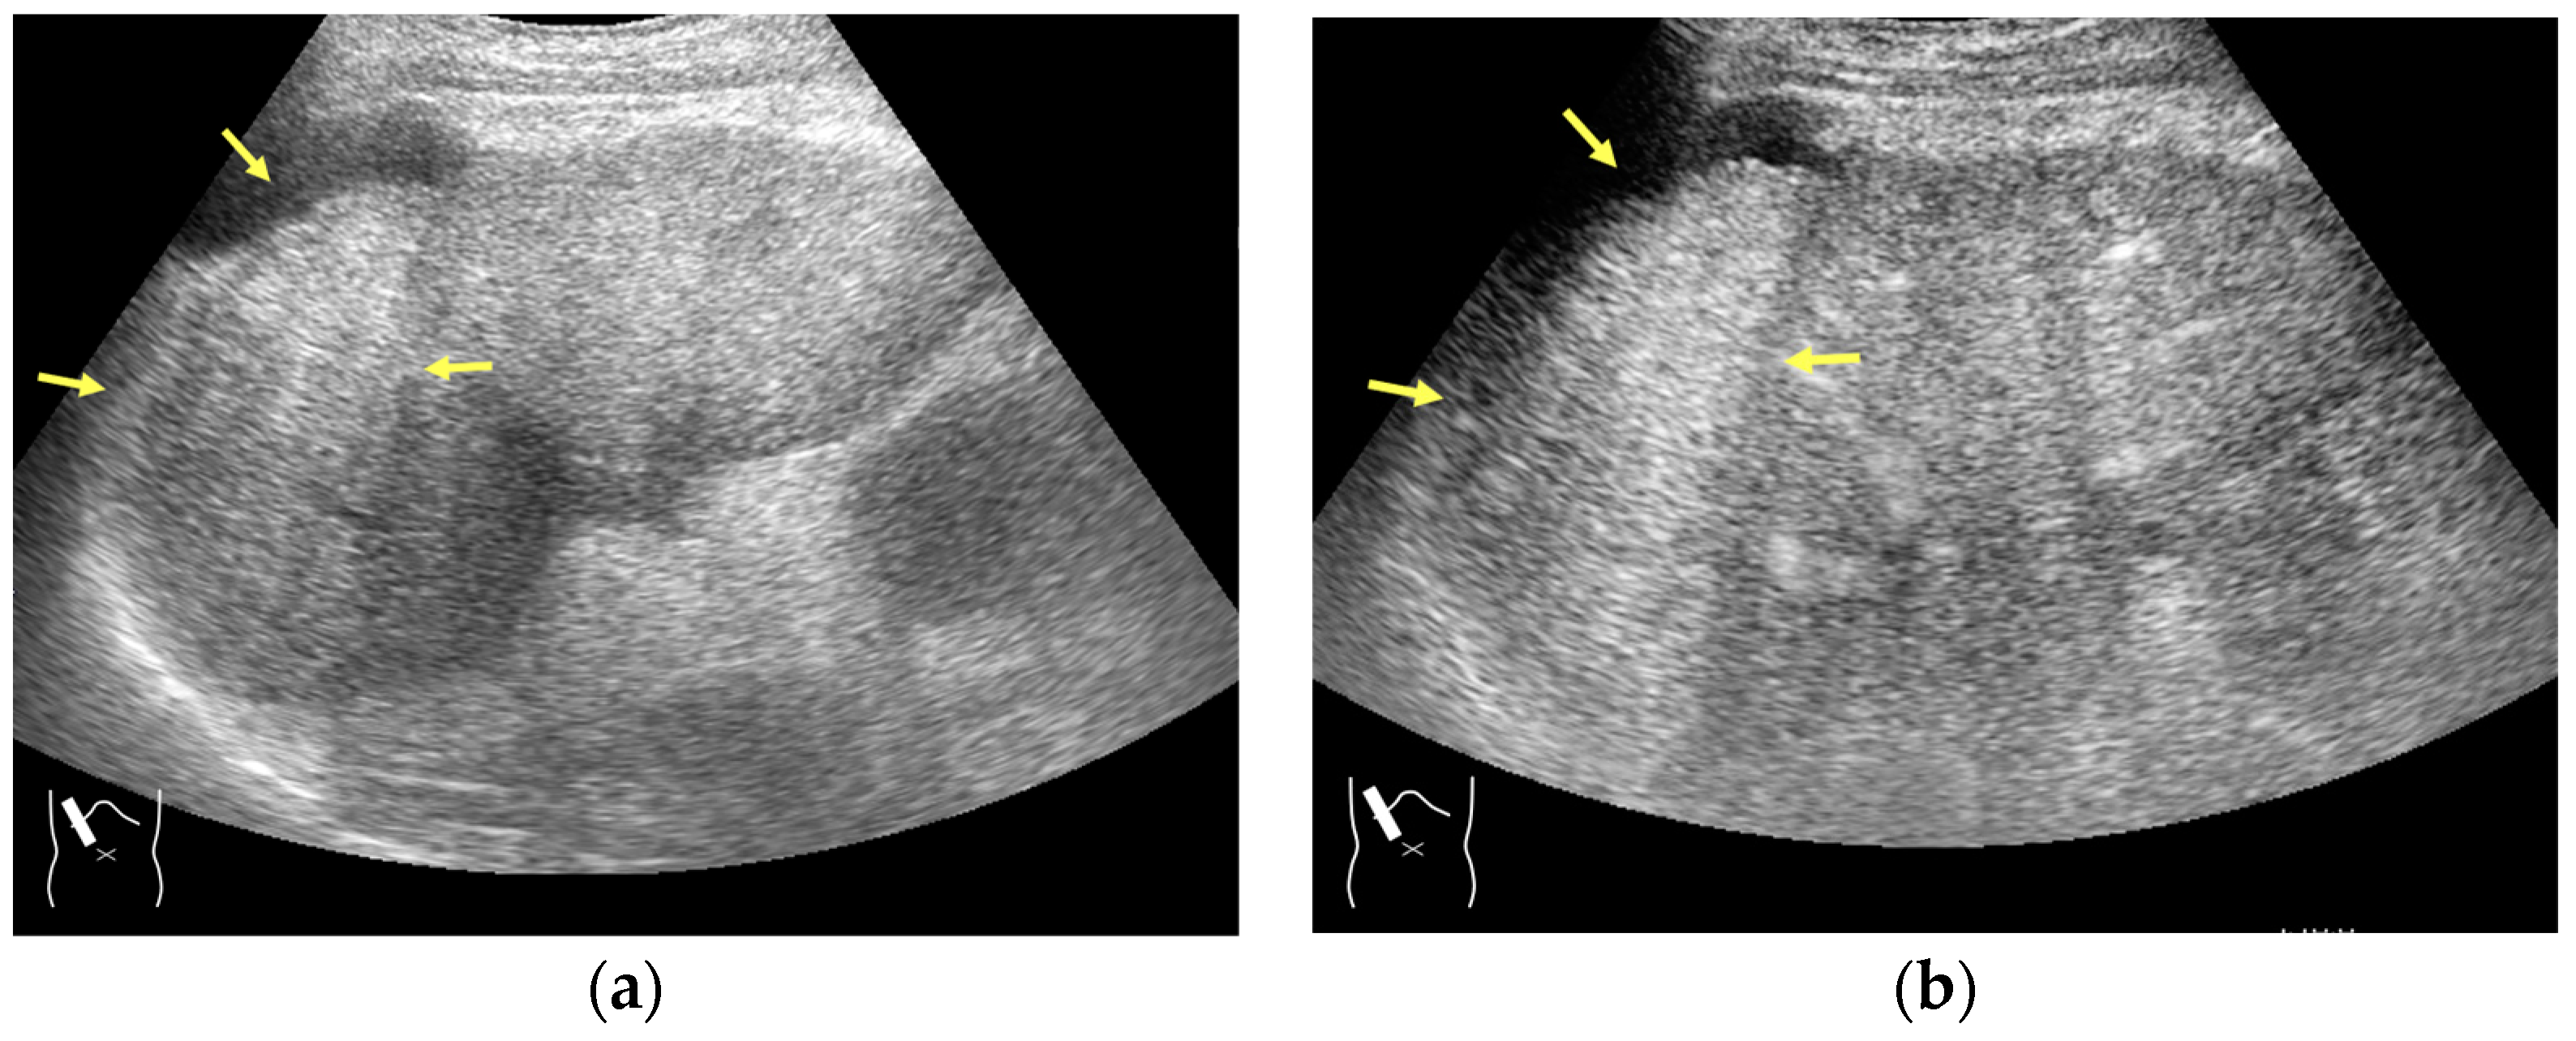

Current US machines reconstruct B-mode US images based on the assumption that sound passes through all parts of human tissues in a straight line and at a constant acoustic velocity (1540 m/s), and this assumption is applied to all scanning planes. The displayed position in a US image usually corresponds with the actual position on the structure. Strictly speaking, however, the acoustic velocity changes according to the tissues [44,45]. Thus, when a plane containing tissues with different acoustic velocities is scanned, sound refraction occurs at the interface between these tissues according to Snell’s law. As a result, the displayed position of point A (the true location) along the line that passes through the interface is falsely displayed at point A’ (a different position) in the B-mode US image as if there was no sound refraction. This refraction artifact is clearly seen in a cirrhotic liver (Figure 3), around a round mass (e.g., a hepatic cyst) (Figure 4) and below the rectus muscles in the transverse scanning plane of the upper abdomen (Figure 5). We will now provide a brief explanation for these three artifacts (Figure 3, Figure 4 and Figure 5). In macronodular liver cirrhosis, sound refraction occurs at the irregular hepatic surface, resulting in the improper positioning and display of echo brightness in the US image [44,45,46], giving the appearance of a “tricolor flag” [46] (Figure 3). When a US beam passes through a mass with an acoustic velocity different from that of the surrounding hepatic parenchyma, it changes direction twice due to sound refraction, first at the liver parenchyma–mass lesion entrance interface and again at the mass lesion–liver parenchyma exit interface. The liver structure behind the mass lesion thus appears to be deformed in B-mode US and heterogeneous in CEUS (Figure 4). As has been reported, sound refraction occurs most clearly at both edges of a mass lesion, and the degree of sound refraction is nearly proportional to the incidental angle of the US beam striking the liver parenchyma–mass lesion interface. Globally speaking, the degree of sound refraction is accentuated as the US beam strikes peripheral to the mass lesion. This is why the posterior echo behind the mass lesion is not homogeneous, as observed in Figure 4. In the transverse scanning of the upper abdomen, the US beam is largely refracted, first at the anterior wall of the rectus muscles and then at the posterior wall of the muscle (Figure 5c). As a result, the liver below the rectus muscles is more or less deformed in B-mode US and CEUS, as seen in Figure 5a,b. The most useful prevention strategy is to use the reference B-mode image (the so-called dual-image technique), which allows for a simultaneous comparison between the CEUS and B-mode images.

Figure 3.

Refraction artifact (1): many vertical bands of different echogenecities in macronodular cirrhosis. (a) Gray-scale US reveals that the left hepatic lobe is markedly deformed with an irregular surface. The liver gives the appearance of a tricolor flag. (b) CEUS shows the liver to be composed of many vertical bands of different brightness (arrows), giving the appearance of a tricolor flag.

Figure 4.

Refraction artifact (2): heterogeneous enhancement behind a mass lesion (liver metastasis). (a) Gray-scale US shows a 5 × 4 cm liver mass (arrows) in the right lobe. (b) CEUS shows it to be enhanced (black arrows, mass lesion). The liver parenchyma behind it is also coarsely enhanced (arrowheads). (c) A schematic drawing of sound refraction through a round mass (black circle) shows that the US beam is refracted twice at the liver parenchyma–mass lesion interface. Non-refractive lines are marked with solid and dashed pink lines. When the acoustic velocity in the mass is less than that in surrounding tissue, it is indicated with an orange line. When it is greater than that in surrounding tissue, it is indicated with a green line.

Figure 5.

Refraction artifact (3): hypoenhanced lines due to US refraction. (a) CEUS shows many hypoechoic lines throughout the liver parenchyma via transverse scanning (arrowheads). (b) The liver’s left lobe shows none of the lines seen in (a) via sagittal scanning. (c) A schematic drawing of sound refraction due to rectus abdominus via transverse scanning plane. The US beam changes direction twice, first at the surrounding tissue–rectus muscle interface, then at the rectus muscle–surrounding tissue interface.